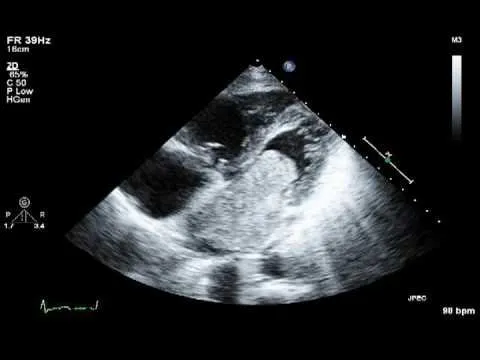

• Siêu âm tim: Đây là phương pháp chẩn đoán hình ảnh quan trọng nhất, giúp xác định vị trí, kích thước, hình dạng và mức độ di động của khối u. Siêu âm tim qua thực quản (TEE) cho hình ảnh rõ nét hơn so với siêu âm tim qua thành ngực (TTE).